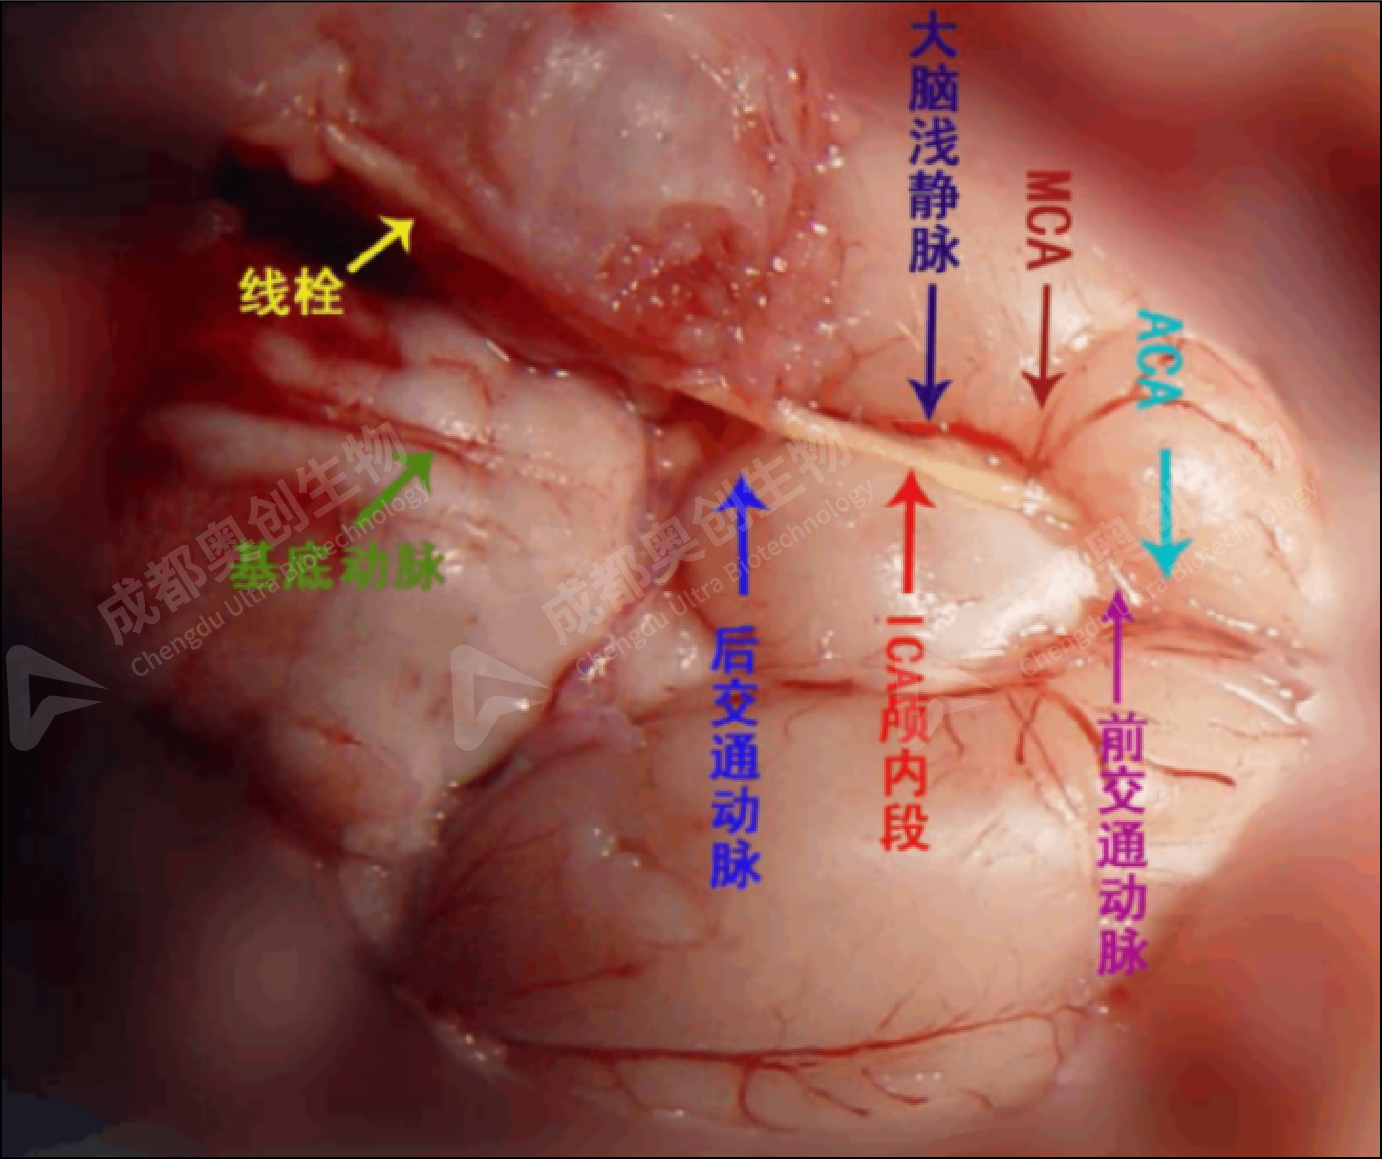

(6)将线栓从切口处插入,当线栓进入到颈内动脉后,拉紧准备好的4-0缝合线防止出血,松开动脉夹,将线栓轻轻送入到大脑前动脉,此时线栓大概进入18mm(18mm的标志刚好在交叉口)。再将拉紧的4-0缝合线打上死结,防止线栓脱出。

(8)2小时后使用麻醉机麻醉大鼠,在保持麻醉状态下拔出线栓至感受到明显阻力,线栓硅胶头由MCA处退至线栓插入口。